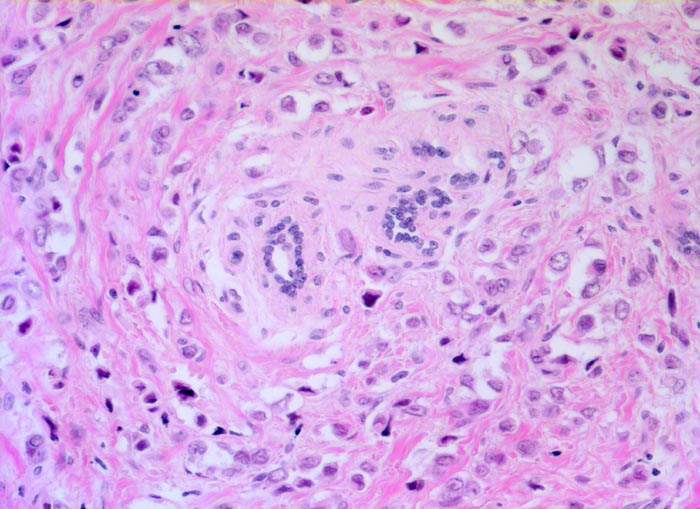

PathoPic ID 5244 - Invasives lobuläres Mammakarzinom

Invasives lobuläres Mammakarzinom

Die recht monomorphen und nicht sehr grossen

Tumorzellen sind in einreihigen Ketten konzentrisch um ein

vorbestehendes Läppchen angeordnet.

Mammographisch suspekter Herd im äusseren oberen Quadranten. Probeexzision.

Histologie

200